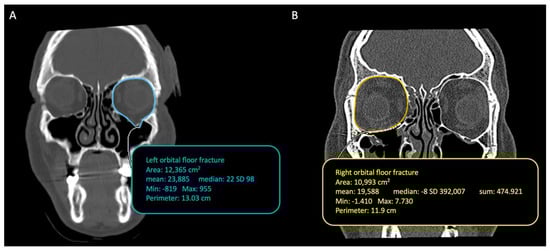

Using the option ROI (region of interest) and selecting the tool “closed polygon”, present on the software Osirix, we could manually identify and delineate the regions of interest for each section of the cut. This was done using the reference points in the posterior to the anterior direction (from the apex to the base of the orbit). Figure 2A shows the preoperative orbital volume measurement including herniated soft tissues. Instead, Figure 2B shows the measurement of the postoperative orbital volume; we performed the measurements following the neo-floor (following the titanium mesh).

Figure 2.

(A) Preoperative orbital volume measurement including herniated soft tissues. (B) Postoperative orbital volume measurement.